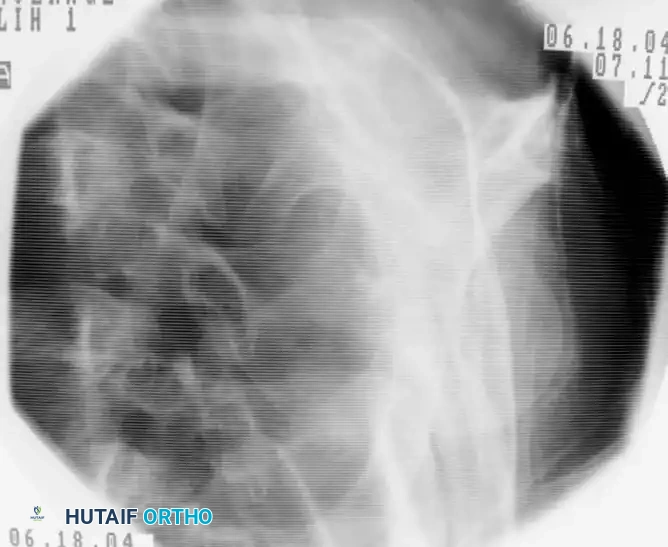

1. Guidewire Placement and Entry Point

The entry point is the most critical step of the operation. An eccentric entry point will lead to malalignment (typically varus) upon nail insertion.

* Identify the bicipital groove. The entry point should be posterior to the biceps tendon.

* Position the starting awl or initial guidewire at the apex of the humeral head, just medial to the greater tuberosity footprint.

* Advance the guidewire under orthogonal fluoroscopic guidance down the center of the humeral shaft.

Fluoroscopic lateral view confirming the central placement of the guidewire within the humeral canal.